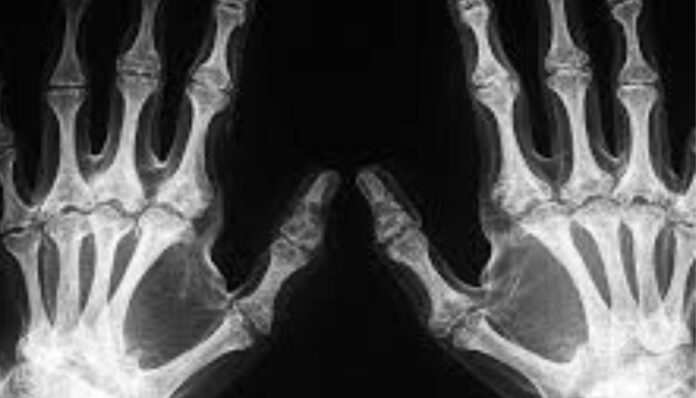

Scientists uncover the ‘acquired habit’ behind the human handedness puzzleResearchers from the Chinese Academy of Sciences have proposed the “Hypothesis of Acquired Conservation of Right-Hand Preference. ” The study suggests that handedness is not something we are born. ..